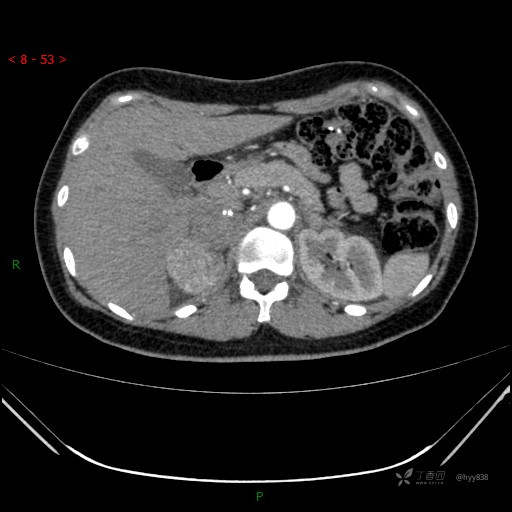

动脉期